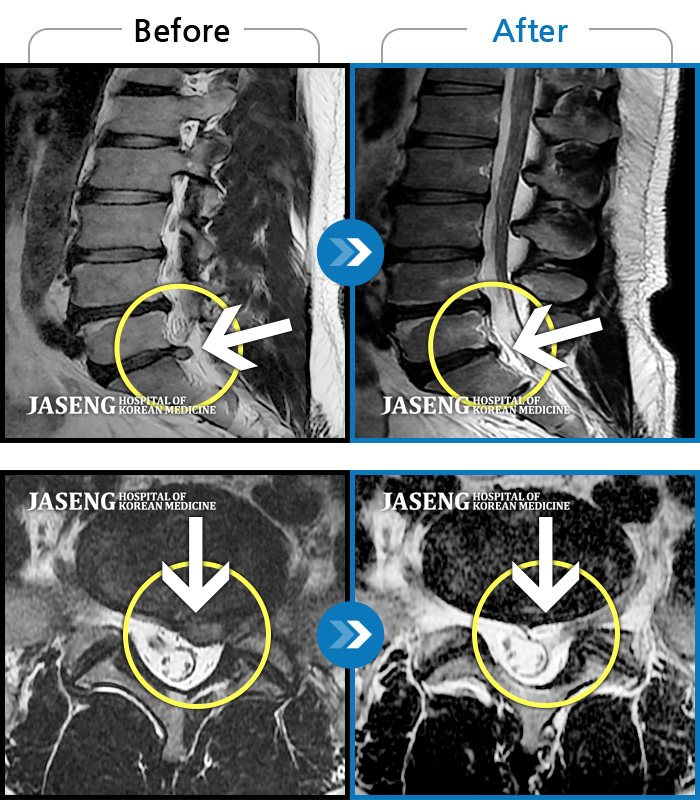

허리디스크

해운대 · 김상돈 원장

허리 골반 통증이 있고 허리를 숙일 때 불편합니다.

촬영시기

2020.09.14 ~ 2025.07.09

2025.07.11

조회수 325